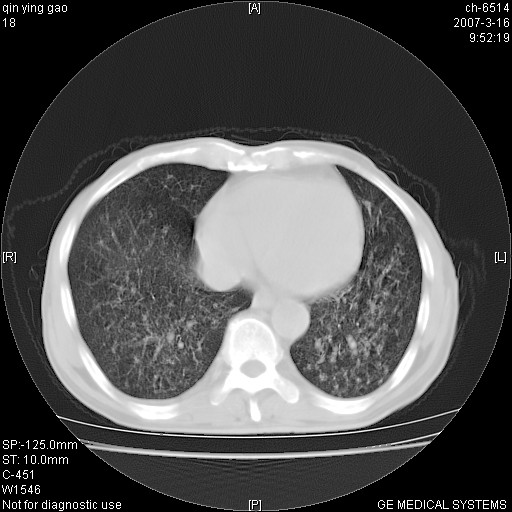

男,64岁.乏力2个月,畏寒、发热1月余。体重下降。血沉加快,白细胞不高。

两中上肺见有广泛新老不一的结节灶,并伴有纤维索条影,血沉加快,白细胞不高,首先考虑结核。

双肺可见大小不等结节状密度增高影,密度不均,分布不均(双肺上叶为著),亚急性血行播散性肺结核.

(本例特征:以大小不等结节为主,主要分布在双上肺,并部分病灶融合成较大结节,期间搀杂诸多细小结节。从病灶特点与分布形式分析,更趋向于感染。)

以双肺上叶为主的弥漫型斑片状密度增高影,边界欠清晰,其中伴有钙化灶,病人有发热史,首先考虑感染性病变:1特殊类型感染,2结核。建议治疗后随诊复查,除外肺泡癌

两中上肺见有广泛分布大小不一的结节灶及斑片状影,部分融合,双下肺未见异常密度影,纵隔无明显肿大淋巴结,血沉加快,白细胞不高,首先考虑结核。 建议结合ppd检查或痰培养排除其他非特异性炎症。

中上肺野密布棉团状影,以胸膜下区为界,边缘模糊,可能是小叶或腺泡渗出及实变。全肺野弥漫分布网线样影及细小粟粒样影,可能是细支气管炎及间质内炎症。综合分析应首先考虑气道播散性感染,而肺内多处斑点性钙化,强烈提示陈旧结核复发并支气管播散。建议详细讯问病史

病变以两肺上野为著,部分病灶有钙化,纵隔窗显示病灶有新老不一,这个首先和结核脱不了干系,还有部分病灶有融洽的倾向,肿瘤也不能完全排出